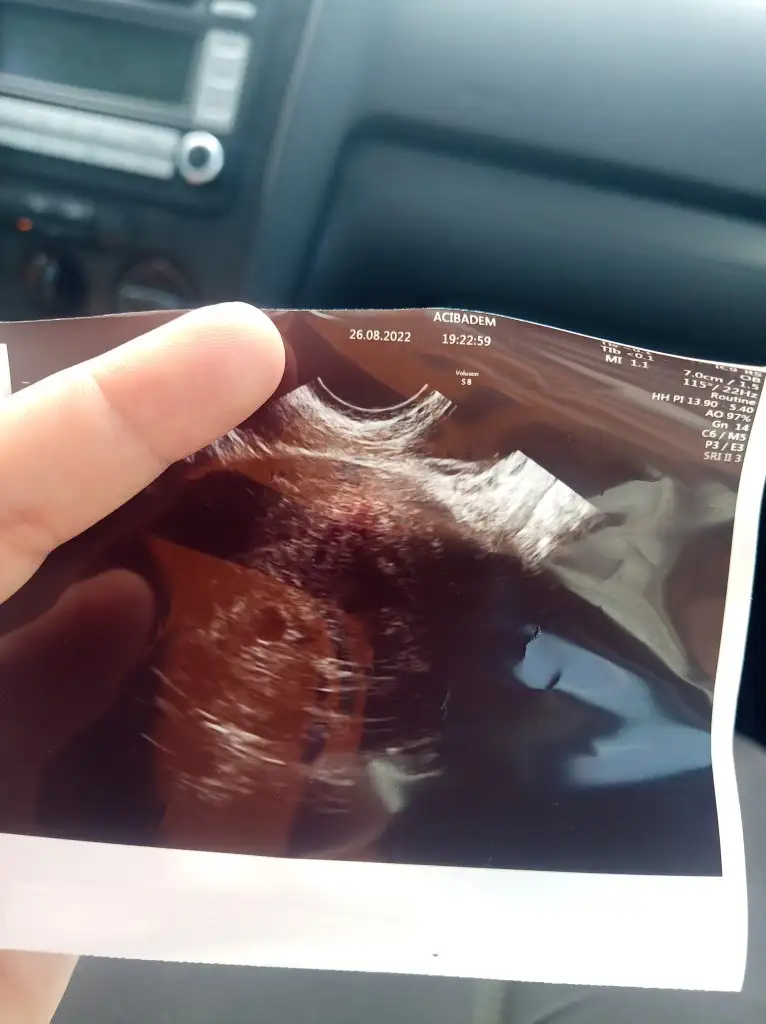

Bugün bende keseyi ve bebeği gördüm çok şükür kabuslarin bı kısmını atlattım dış gebelik mi boş gebelik mi ömrümü yedi on gündür bugunumuze şükür Rabbim dileyen herkese tattirsin bu duyguları amin

DİPNOT:Çok çekince çok ağlanıyormuş bı nevi sinir boşalması😁